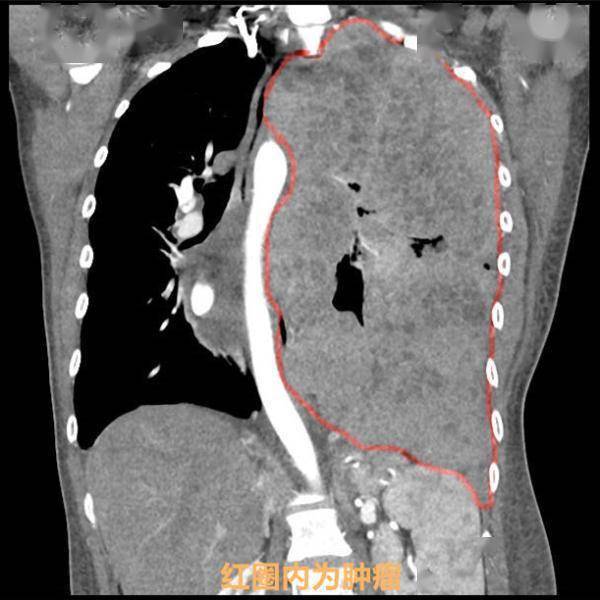

2个月前 , 她气促症状加重 , 同时出现胸闷、胸痛 , 双下肢水肿 , 睡觉时不能平躺 , 到当地医院进行CT检查后 , 结果令她大吃一惊 , 左侧胸腔内长出一个约29厘米的巨大肿瘤 。

该肿瘤几乎完全占据了她的左侧胸腔 , 不仅把她左肺完全压缩了 , 还把心脏和纵膈大血管结构挤压至对侧 , 脊柱也因为肿物的挤压而发生侧弯 。

红圈左肺位置 , 被肿瘤侵占 。 通讯员供图